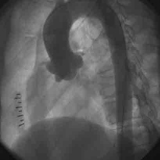

肌性室間隔缺損室間隔肌部缺損臨床上少見,目前亦採用介入封堵治療。

病因 症狀 檢查 治療 鑑別室間隔肌部缺損臨床上少見,目前亦採用介入封堵治療,術後行心電監護7天,並每天記錄心電圖;青黴素360萬U/天,共3天;地塞米松10mg/天,共5天;口服...